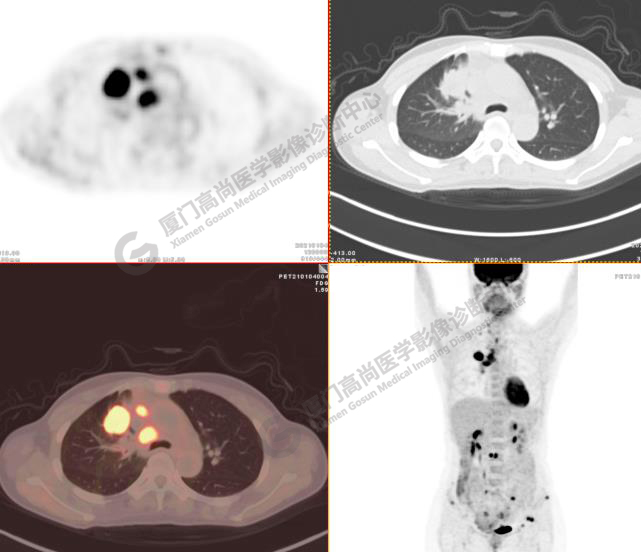

病例3:某女,47歲,咳嗽3周,無咯血,右上胸部疼痛,腰部疼痛

右肺上葉前段實(shí)性腫塊,大小約3.2x2.7x2.6cm,邊緣見毛刺、分葉,胸膜牽拉明顯,前段支氣管阻塞。FDG攝取增高,SUVmax,16.8;右側(cè)頸部Ⅳ區(qū)、右側(cè)鎖骨區(qū)、右肺門及縱隔淋巴結(jié)腫大, FDG攝取增高,SUVmax7.9;C2、L2椎體、右側(cè)第6肋骨、骶骨、髂骨、左側(cè)髖臼、腰椎體及附件骨質(zhì)破壞,SUVmax11.8。

影像診斷:右肺上葉周圍型肺癌并多發(fā)淋巴結(jié)、骨骼轉(zhuǎn)移。(TNM分期,T2aN3M1c  Ⅳ B期)

病理診斷:低分化腺癌